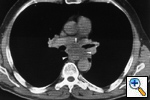

Fig. 26a: Computed tomographic scan of the chest shows enlarged subcarinal nodes (white arrowheads) that deviate the esophagus posteriorly and laterally, N2.